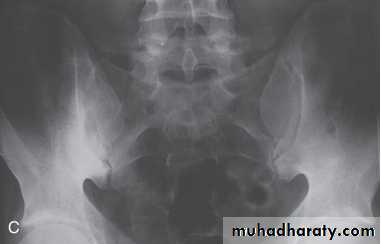

In established AS, radiographs of the sacroiliac joint show irregularity and loss of cortical margins, widening of the joint space and subsequently sclerosis, joint space narrowing and fusion.

Erosive changes may be seen in the symphysis pubis, the ischial tuberosities and peripheral joints.